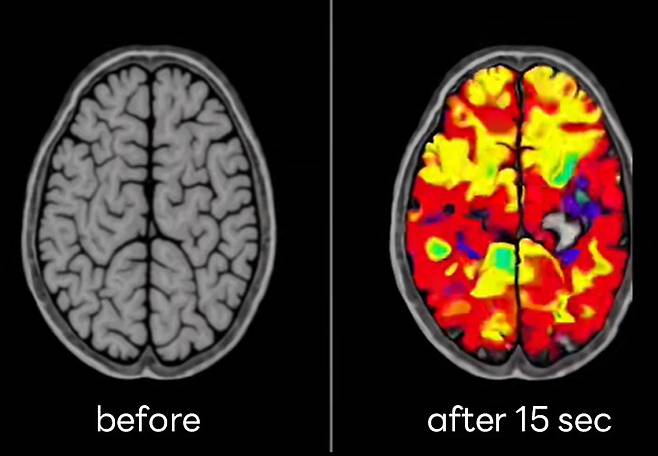

미국 전역에서 난리난 15초 만에 뇌가 맑아지는 주파수